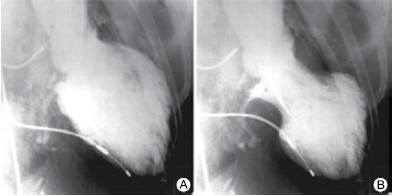

Mulher, 75 anos, apresenta dor torácica de forte intensidade após o falecimento do marido. É levada ao serviço de emergência onde eletrocardiograma mostra supradesnivelamento do segmento ST de V1 a V6. Encaminhada para hemodinâmica que mostra os seguintes achados:

Ventriculografia:

(Arquivo pessoal; imagens usadas com autorização)

Assinale a alternativa com o diagnóstico correto.